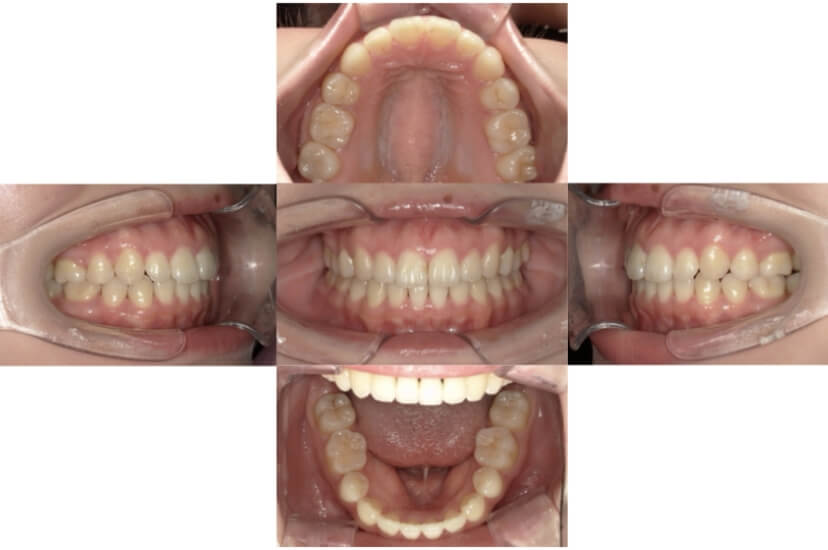

上下顎叢生(上下の前歯のガタガタ)のケースです。

装置はラビアル(上下表側)で、上下顎の小臼歯を4本抜歯を行っています。抜歯したスペースを使って、上下の前歯の後方移動と叢生(ガタガタ)の改善を行っています。

主訴 八重歯を治したい。

年齢・性別 25歳 女性

お住まいの地域 神奈川県川崎市

治療方針 抜歯スペースを利用して上前歯の叢生(ガタガタ)の改善

抜歯部位 上下顎左右第一小臼歯

使用装置 ラビアル(上下表側)、顎間ゴム

治療期間 1年11か月

治療回数 16回

BEFORE

AFTER